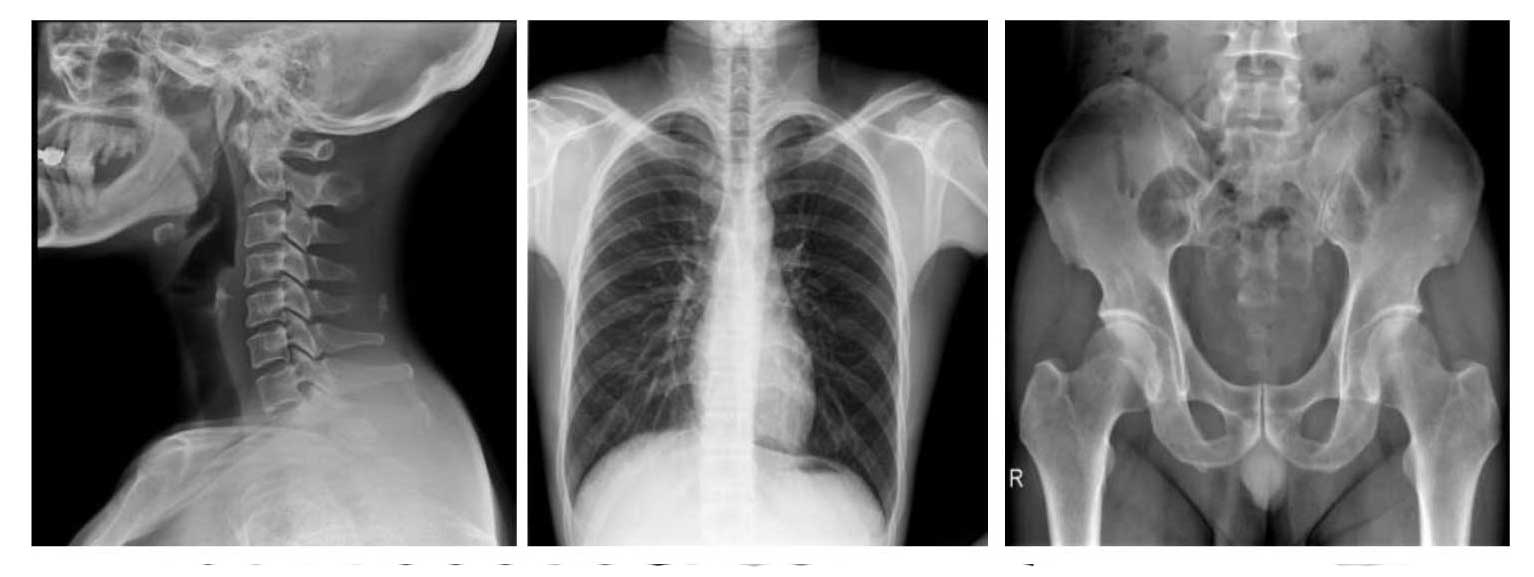

- Применяется для любых клинических рентгенологических исследований, включая специализированную позиционную рентгенографию.

- Высококачественное цифровое изображение с высокой чёткостью и детализацией.

- SID до 1,8 м для проведения рентгенографии грудной клетки, лобной части, крестцово-копчикового отдела и др.

- Автоматическая сшивка изображений (опция): формирование предоперационных планов и оценка послеоперационных результатов (сколиоз, нагрузка на ортопедические изделия, протезирование колена, эндопротезирование тазобедренного сустава).